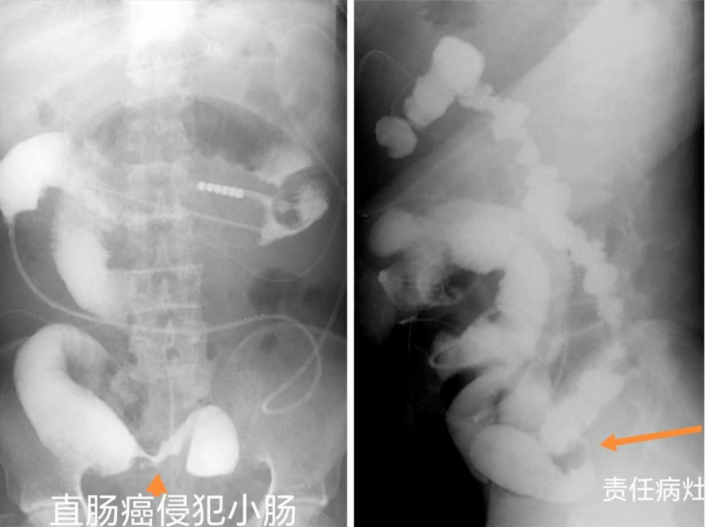

病例分享三

老年男性,既往因“直肠恶性肿瘤”在上级医院化疗2周期后出现肠梗阻。急症在我院行乙状结肠造瘘术,术后给予肿瘤综合治疗,术后约3年再次出现小肠梗阻,经禁饮食、静脉营养、胃肠减压等保守治疗,症状不缓解。经会诊,由肿瘤内科转至普外综合介入科,决定为病人行经鼻型肠梗阻导管减压术,并同期完成消化道顺逆行造影明确病变部位,证实直肠肿瘤侵犯远端回肠,择期拟行手术治疗,解除肠道梗阻。